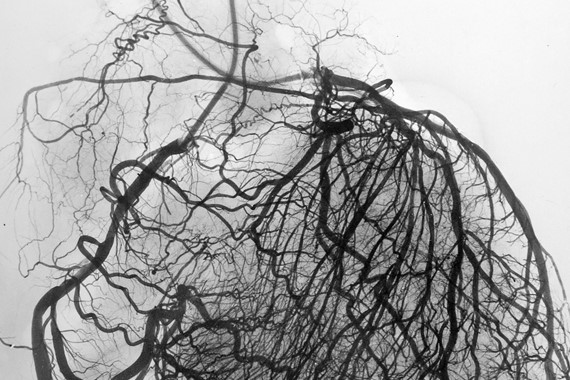

Angina is chest pain that happens when there is a restriction in blood flow to the heart muscle. An x-ray procedure called a coronary angiogram can help to show if there are any blockages in the coronary arteries supplying blood to the heart which can cause this. But the small vessels in the heart are too tiny to be seen with this imaging test.

This is important because the small vessels help to control blood flow in the heart, and there are many more small vessels than large vessels. This can be seen in the ‘stereoangiogram’ image above (by Dr William Fulton, University of Glasgow) - which provides more detail than a standard coronary angiogram.